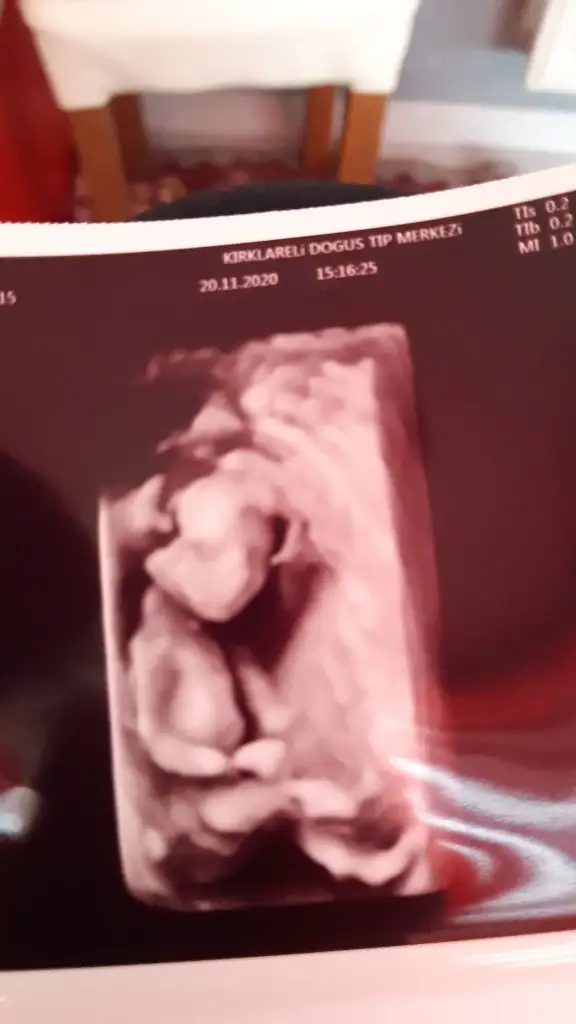

Allah bağışlasın18 haftalık olduk biz de artık cinsiyetimiz kesinleşti bir oğlum vardı bir erkek daha geliyorBugün de nifty testimin sonucu cıktı şükür bir risk saptanmamış Eki Görüntüle 2724286